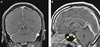

QUAIS OS ACHADOS DA RNM DA HIPERTENSÃO INTRACRANIANA IDIOÁTICA?

A

How well did you know this?

9

Q

HIPOTENSÃO INTRACRANIANA

- Quais os achados da RNM?

Espessamento da paquimeninge: principalmente

Aumento da hipófise

Derrame subdural

Redução da distância mamilopontina

Achatamento do tronco encefálico

MNEMONICO:

S: subdural fluid collections

E: enhancement of the pachymeninges

E: engorgement of the venous sinuses

P: pituitary hyperemia

S: sagging brain

Ataques frequentes* e incapacitantes

*>2 ou 3 dias por semana por 6 - 12 meses